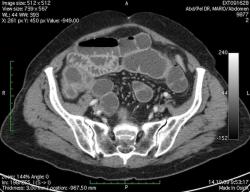

КТ брюшной полости. Женщина 73 года с жалобами на запоры.

Пациентка женщина 73 года. Предъявляет жалобы на запоры, спастические боли в брюшной полости.

ИзображениеЦиркулярное сужение в поперечной ободочной кишке. Ни это ли причина проблемм?

Новообразование в среднем отделе поперечной ободочной кишки с циркулярным сужением просвета и хронической механической толстокишечной непроходимостью. Признаков метастазирования в данной анатомической области не обнаружено. Пациент безусловно нуждается в хирургическом лечении.

Я не занимаюсь КТ, но сам характер сужения толстой кишки как-то вызывает сомнения, ракового ли он характера? Сужение то циркулярное, но больно уж ровненькое и нет признаков инфильтрации вокруг (хотя рак, конечно может иметь и такой вид). Ну, думаю dr.Mario со временем откроет карты и будет дана гистология.

Циркулярная стенозирующая опухоль (аденокарцнома) толстого кишечника; с типичной КТ презентацией и признаками обструкции. Пациентка была оперирована на второй день после КТ.